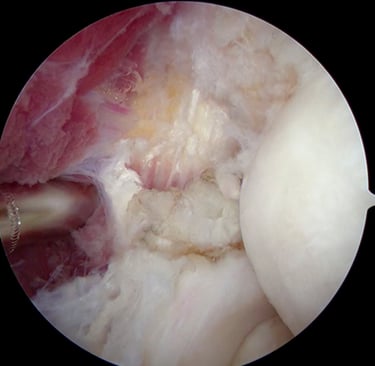

Hangi Durumlarda Ameliyat Gerekir?

Aşağıdaki durumlarda cerrahi değerlendirme gerekir:

Diz kilitlenmesi

Parça kopması (bucket handle yırtık)

Şiddetli ve geçmeyen ağrı

Sporcu yaralanmaları

Mekanik takılma hissi

Bu durumlarda artroskopik cerrahi düşünülebilir.